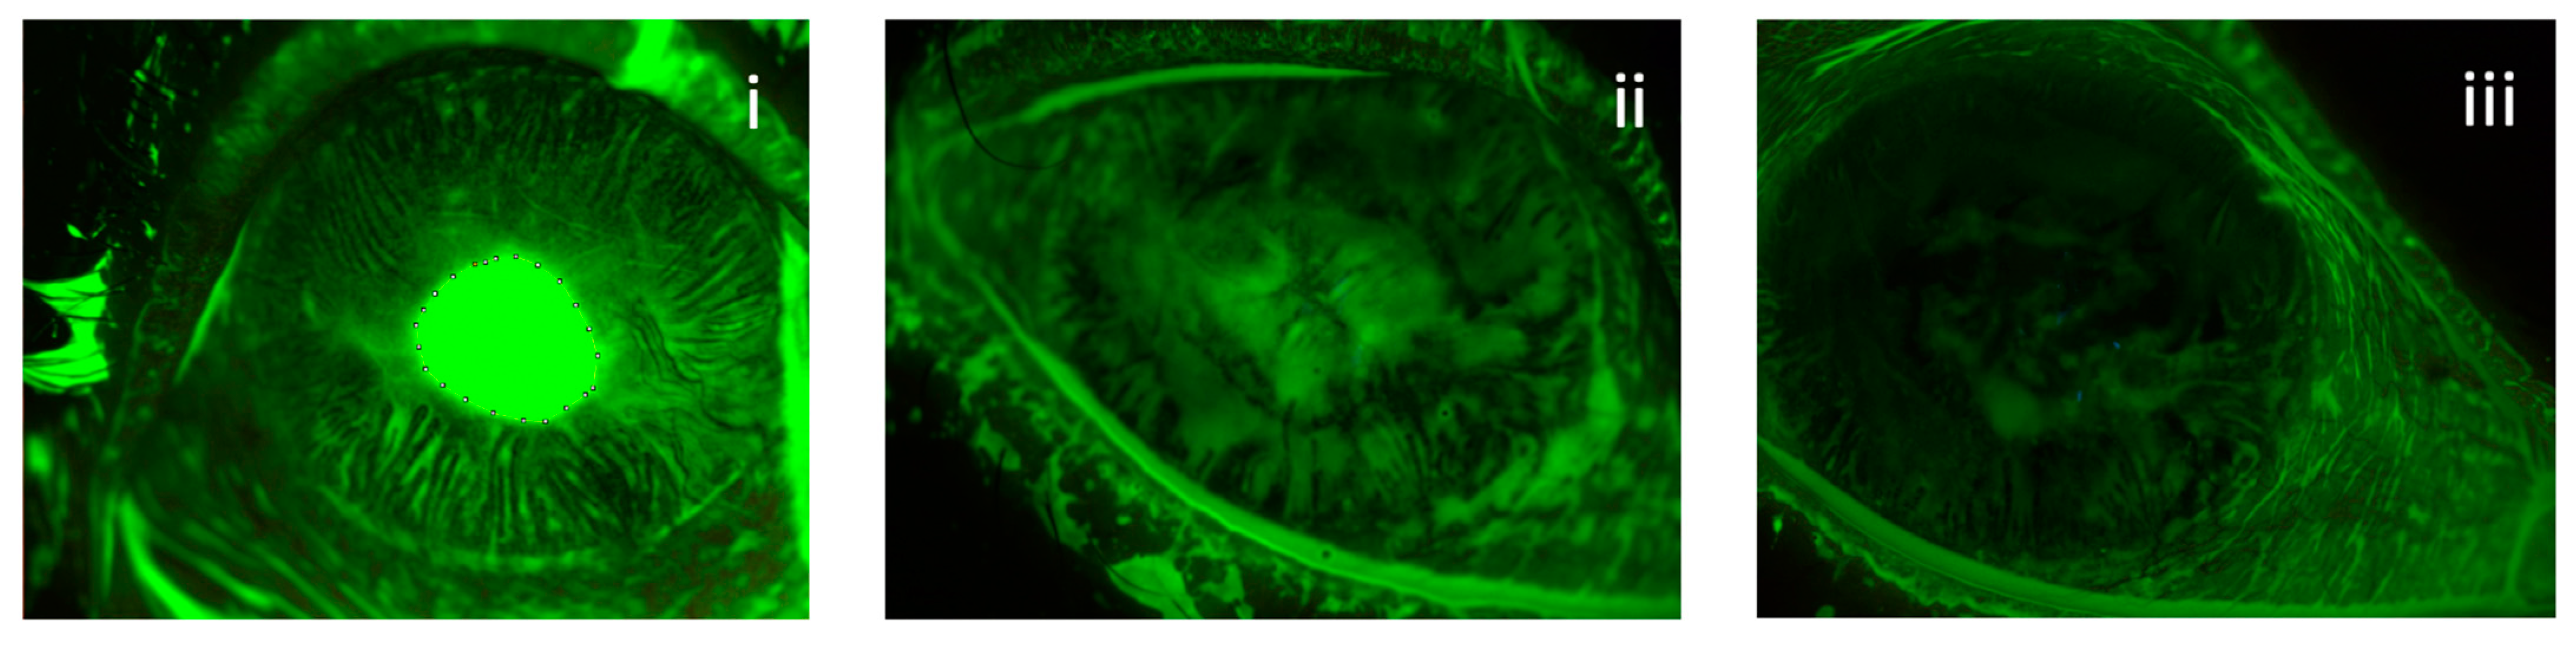

According to K5M data, after 4 weeks of the treatment, the ulcers healed completely in 69% (9 of 13) of eyes and at 8 weeks a complete recovery was registered in 100% of eyes (13 of 13) (Figure 1).

Figure 1.

Reduction in ulcer’s area in a patient with post-herpetic NK treated with rh-NGF. The extension of the defect was calculated with ImageJ software at baseline (i), 4 weeks (ii) and 8 weeks (iii).